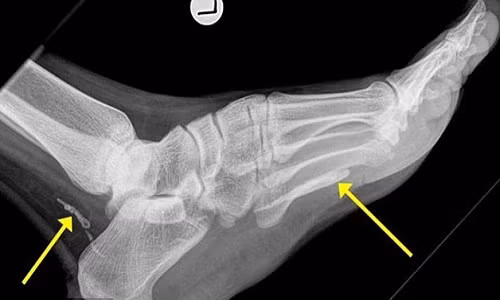

| Ảnh chụp X-quang cho thấy các mảnh giun phân hủy trong bàn chân bệnh nhân. |